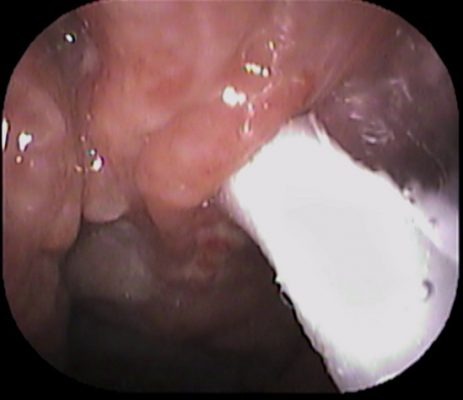

まずは、鼻👃から

極めて軟らかい組織で出血量も多かったです。